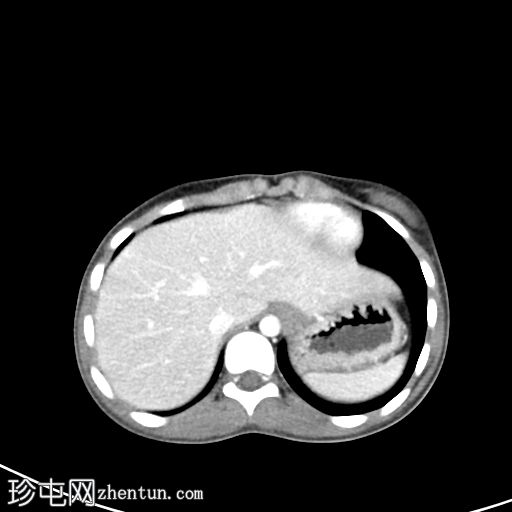

轴向C+门静脉期

可见明显扩张的充满液体的结构从阴道管延伸,与宫颈相通,进入中度扩张的子宫内膜腔,其上缘位于L4椎体。

内容物为均匀的高衰减液体(约35-55 HU),与血液密度一致。

该液体使膀胱向前移位,并移位邻近的肠管。

无腹部游离液体、肠梗阻、淋巴结肿大或肾积水的证据。